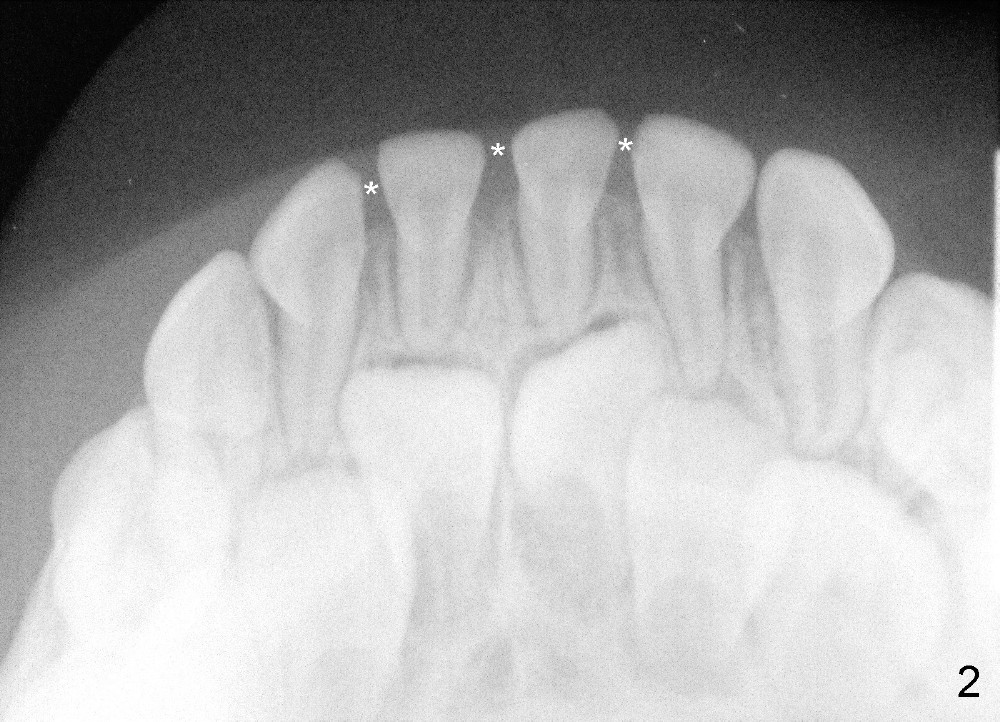

Devon's 9-year-old sister has basically normal tooth alignment, whereas 4-year-old sister has single-tooth cross bite (Fig.3 D, deciduous lateral incisor). Other than that, the younger sister is fine (Fig1, upper occlusal) with normal spacing between deciduous teeth (Fig.2 (lower occlusal): *).

Devon(男孩)的姐姐(九岁)牙齿基本整齐,四岁妹妹有轻度不齐,例如右上乳侧切牙反合(图三:D),除此之外,发育正常,例如出现乳牙间隙(图二:*)。